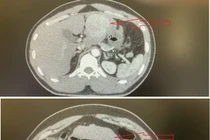

Hình ảnh khối u của bệnh nhi/Ảnh VTV

Tại Bệnh viện Đa khoa Hà Đông, bác sĩ ghi nhận ở hốc amidan trái có khối màu tím sẫm, mềm, có cuống, di động, không sùi loét. Kết quả chụp cắt lớp vi tính cho thấy khối u nghi là u máu, được cấp máu từ tĩnh mạch cảnh trong bên trái. Bệnh viện đã hội chẩn cùng chuyên gia Bệnh viện K và xác định đây là u máu amidan trái - một dạng dị dạng mạch máu lành tính nhưng có thể chảy máu hoặc chèn ép đường thở nếu không xử trí sớm.